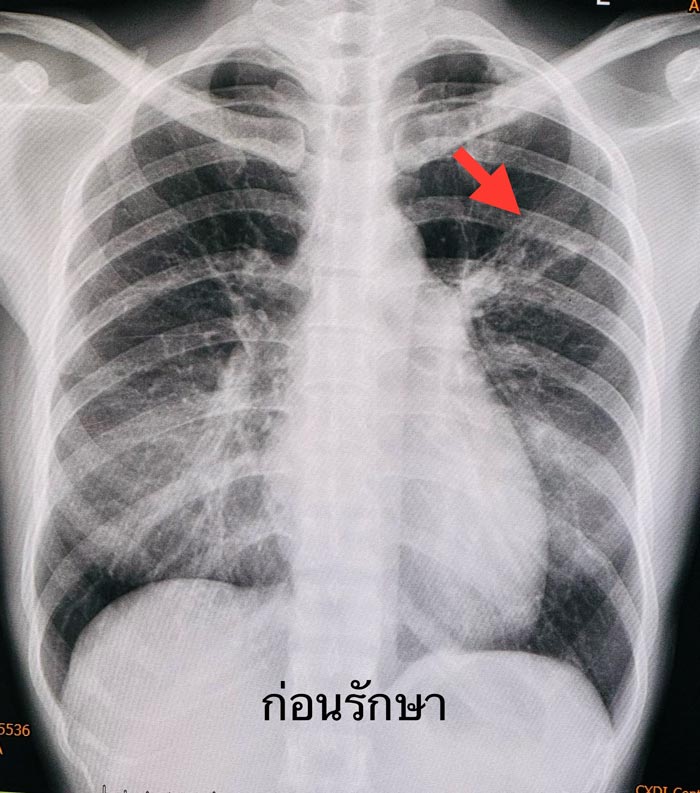

ผู้ป่วยหญิงอายุ 34 ปี ปกติแข็งแรงดี ไม่มีโรคประจำตัว ไม่มีไอเรื้อรัง ไม่มีไข้ ไม่เบื่ออาหาร น้ำหนักไม่ลด ไม่มีเหงื่อออกกลางคืน ไม่เหนื่อย ขณะนอนหลับอยู่รู้สึกมีอะไรอยู่ในคอ ไอออกมามีเสมหะปนเลือด ไม่เจ็บคอ ไม่กินเหล้า ไม่สูบบุหรี่ ไม่เคยใกล้ชิดกับคนเป็นวัณโรค วันรุ่งขึ้นจึงมาหาแพทย์

วินิจฉัย : เป็นวัณโรคปอด เริ่มยารักษาวัณโรค 4 ขนาน คือ INH, rifampicin, pyrazinamide, ethambutol และวิตามิน B6 ผู้ป่วยกินยาได้ดี ไม่แพ้ยา หลังกินยาไม่มีไอเป็นเลือดอีก

1 เดือนต่อมาผลเสมหะเพาะเชื้อวัณโรค ขึ้นเชื้อวัณโรค M.tuberculosis ไวต่อยารักษาวัณโรคทุกตัว ให้ยารักษาวัณโรค 4 ขนานต่อไปจนครบ 2 เดือน แล้วลดยาเหลือ INH, rifampicin และวิตามิน B6 รับประทานต่อไปจนครบ 6 เดือน ผู้ป่วยแข็งแรงดี ไม่มีไอเป็นเลือด เอกซเรย์ปอดปกติ (ดูรูป)

ผู้ป่วยรายนี้ตรวจพบเป็นวัณโรคจากการไอเป็นเลือดเพียง 1 วัน ก่อนหน้านี้ไม่มีอาการอย่างอื่นเลย มาพบแพทย์ทันที ตรวจพบเร็ว รักษาหายขาด